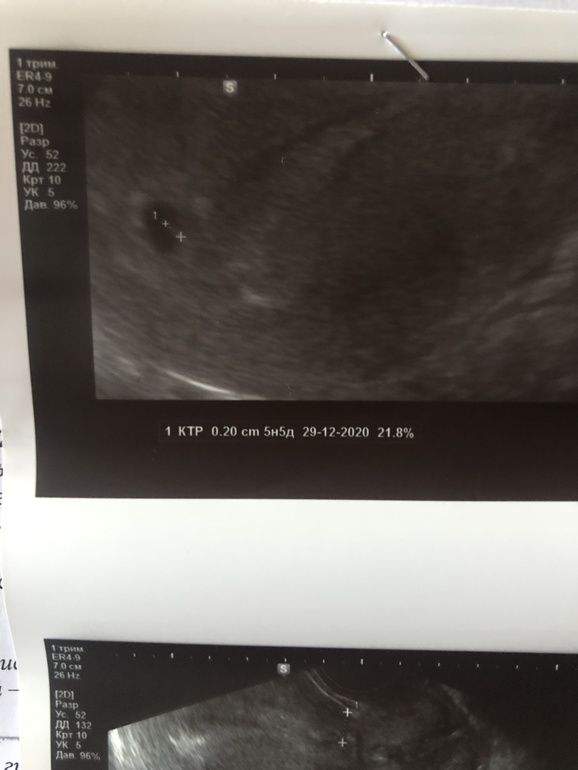

Узи, 5 недель

Ну что) Все хорошо 🙌🏻😌 Бусина в домике, беременность маточная, отслойки нет, в яйце визуализируется крошечный намёк на эмбриона 2 мм. Почему-то нет желточного мешка🤨🤨🤨 Но яичник работает хорошо, желтое тело активно вырабатывается

Все соответсвует сроку ❤️

Фото бусины